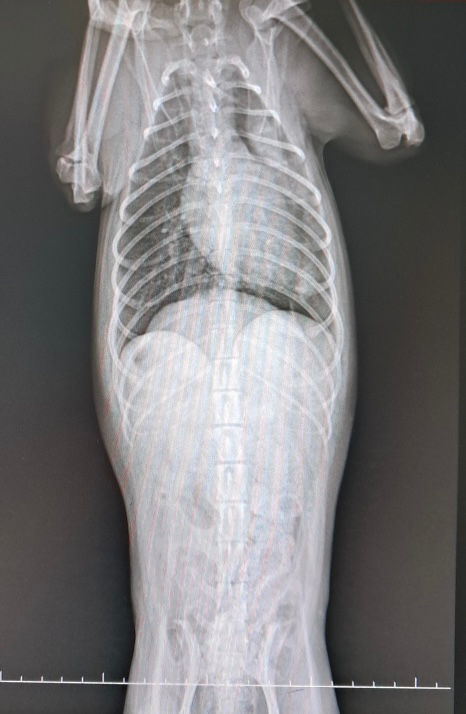

강아지가 외상으로 인해 명절부터 켁켁대서 동네 병원을 가보았는데 엑스레이 찍어보더니 기흉인 거 같다. 큰병원 가봐야 할 거 같다고 합니다.

폐의 심각한 문제가 있는것으로 보이고, 엑스레이사진에서 표현되는것보다 폐는 항상 더 심각한 이상을 보입니다.

개에서는 심장이 이렇게 떠 있는 상황을 좋지 않은 상황으로 고려하기 때문에

첫번째 동물병원의 원장님의 소견을 더 중요하게 여겨야 합니다.